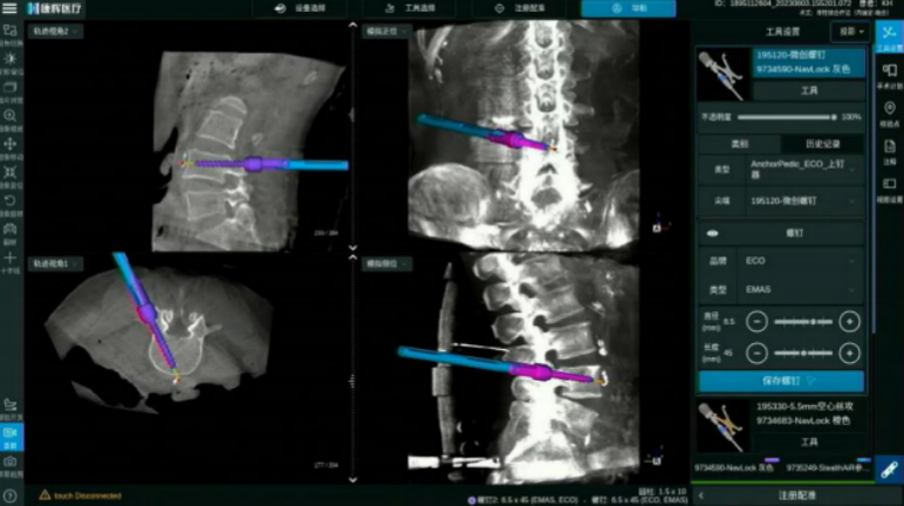

颈椎后路内固定

全程可视化带来颈椎手术精准性的提升

ECO/Anchor与导航化学连接 螺纹级可视

电动手柄配合导航实现可视化动力置钉

· 无导丝置钉流程, 手术更加精准安全

· 开路、丝攻、置钉,手术全程步步实时可视

· 实时呈现手术工具、 内植入物清晰边界

· 可拓展至椎间处理步骤 三维实时可视